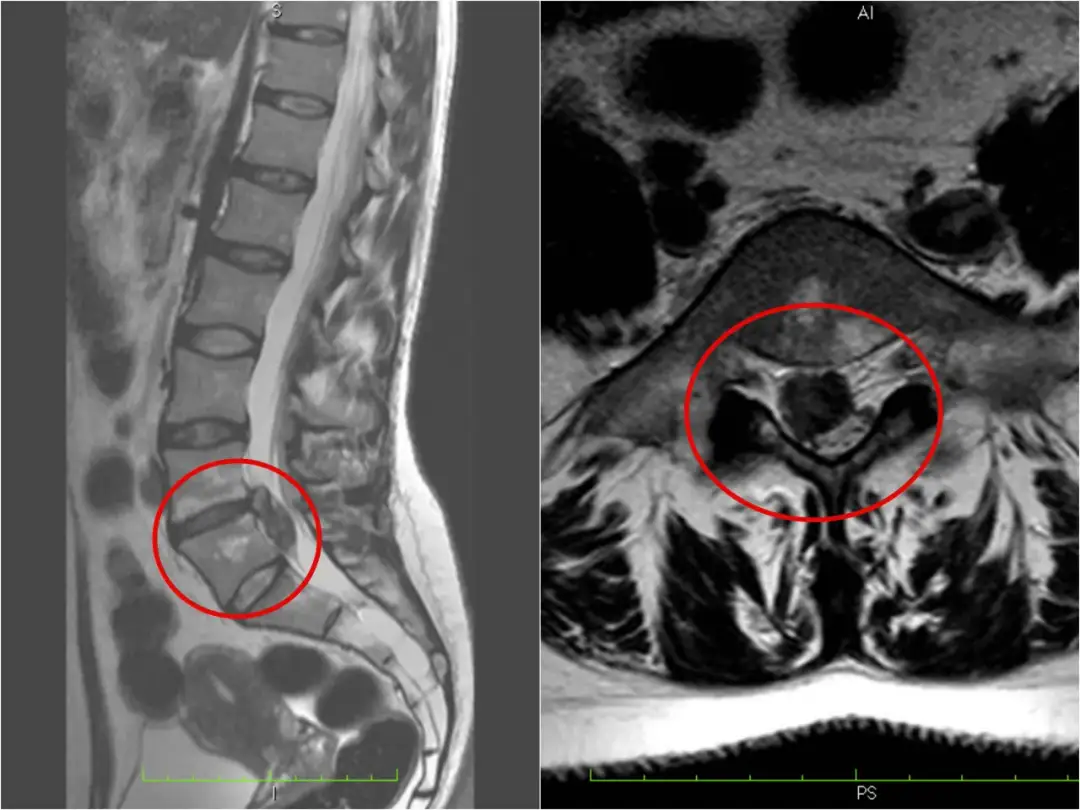

Czy przepuklina kręgosłupa może się cofnąć? Poznaj fakty o spontanicznej regresji, czynnikach wpływających na wchłanianie się przepukliny i roli rehabilitacji w procesie leczenia.

Poznaj kluczowe różnice między wypukliną a przepukliną. Dowiedz się o objawach, diagnostyce i metodach leczenia obu schorzeń. Sprawdź, kiedy konieczna jest interwencja chirurgiczna.